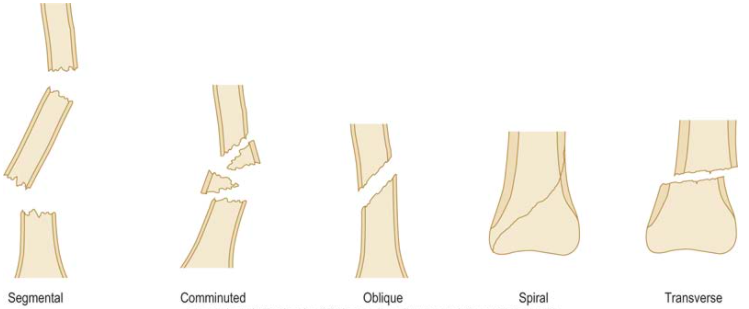

What is the mechanism of injury in a spiral fracture?

Occur due to torsional (twisting) forces

What is the mechanism of injury in a comminuted fracture?

Generally a reflection of a higher energy injury (or poor bone quality)

What is the mechanism of injury in an oblique fracture?

Occur with a shearing force

What is a segmental fracture?

Very unstable fracture that occurs when the bone is fractured in two separate places

What is the mechanism of injury in a transverse fracture?

Occur with pure bending force where the cortex on one side fails in compression and the cortex on the other side in tension